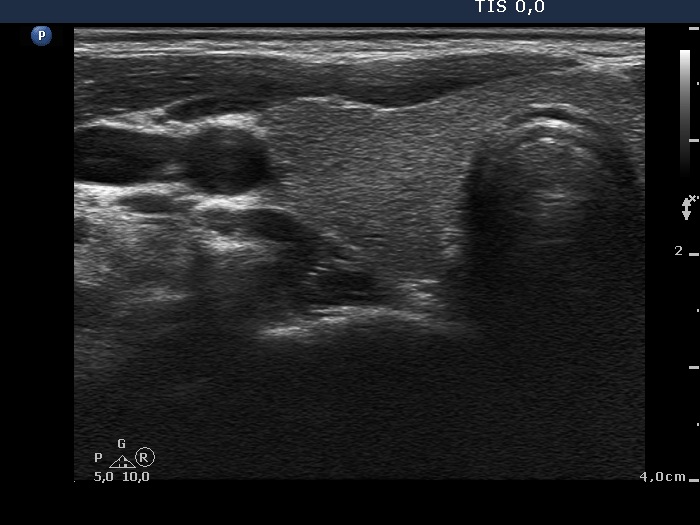

Ultrasonography: The thyroid was echonormal. There was a moderately hypoechogenic inhomogeneous nodule in the lower pole of the right lobe. There were two lymph nodes next to each other above the right thyroid in the submandibular area. The lymph nodes presented a regular hilum.

This is the typical presentation of a bacterially infected lymph node. In most of these cases we find multiple lymph nodes next or very close to each other. The presence of ill-defined hypoechogenic areas within the lymph nodes is an even more important sign of a bacterial lymphadenitis.